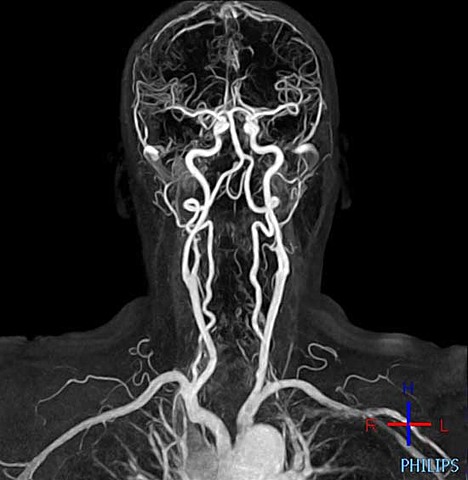

• Sistema Vascular

Sistema Vascular

Dr. Moses Swick, un urólogo estadounidense y Alexander Von Lichtenberg en Berlín, probó el uroselectan. Este fue un avance importante en la investigación del sistema vascular, y permitió la realización de la pielografía intravenosa.

• Resonancia Magnética

Resonancia Magnética

Fue posible la resonancia magnética gracias al trabajo de Edward Mills Purcell (Premio Nobel de Física en 1952), Paul C. Lauterbur (Premio Nobel de Medicina en 2003), Raymond V. Damadian y colegas, como también el investigador británico Sir Peter Mansfield (Premio Nobel de Medicina en 2003).